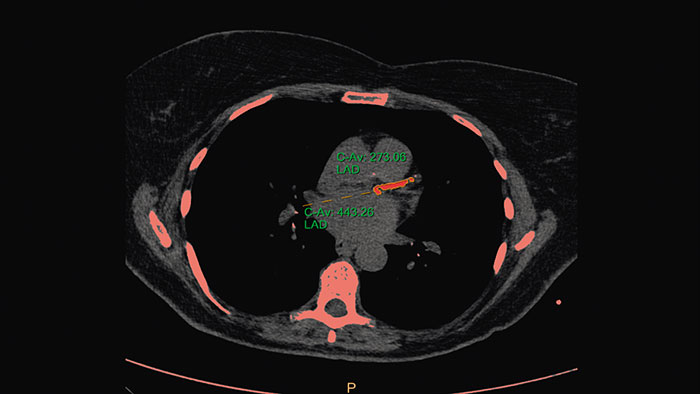

Calcium Scoring

CT Calcium Scoring

One-click 3D calcium segmentation

One-click 3D segmentation and quantification for coronary arteries calcifications including mass, Agatston, and volume scores.

Benefits

• Calcium scoring is achieved by performing automatic calculations on CT HU values in user-defined regions of interest.

• Supports ECG-gated and non ECG-gated images in DICOM format from Philips and other vendors (mass score can only be calculated for Philips CT scanners).

• The application incorporates parameters from the MESA (Multi Ethnic Study of Atherosclerosis) database.